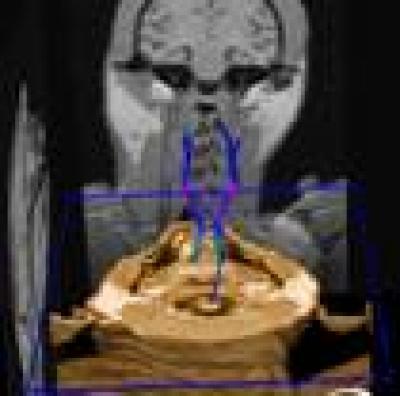

This corticospinal tract from a monkey brain can be seen to originate in the precentral gyrus, continue down through the internal capsule, and then down to the midbrain and medulla oblongata. Each fiber tract is continuous and uniform in the shape.

(Photo Credit: Neural Regeneration Research)